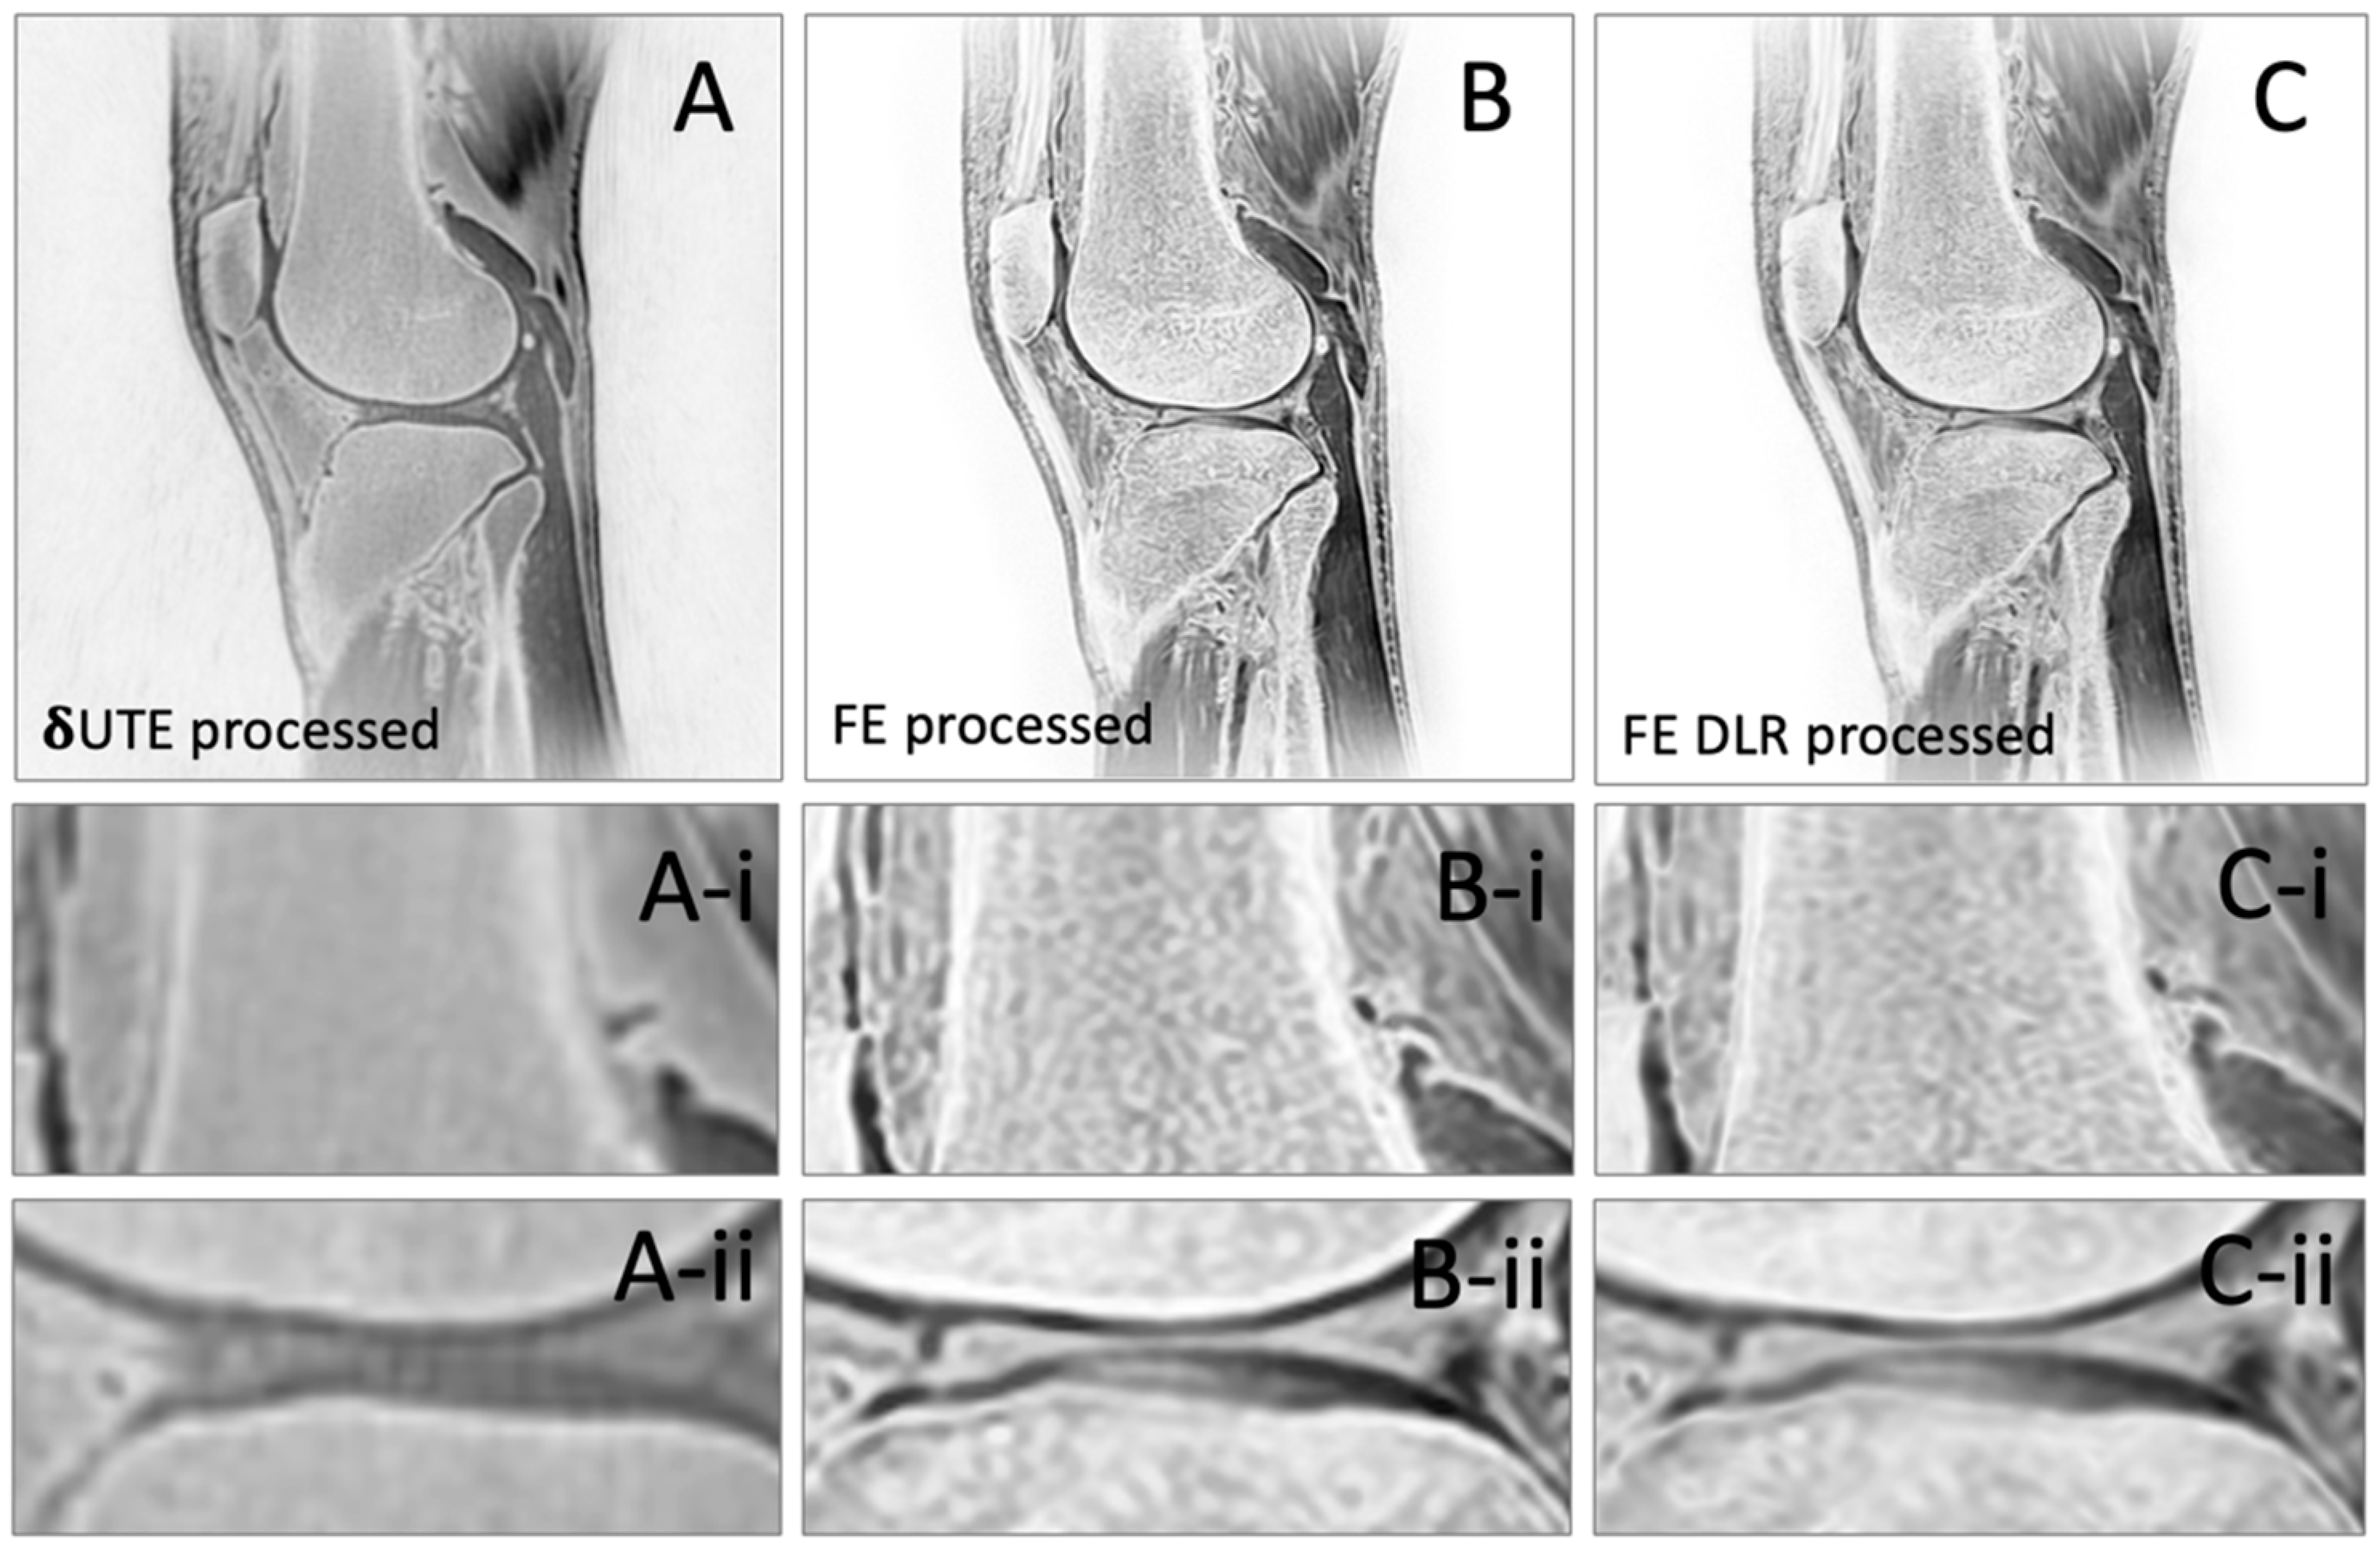

| Measurement | δUTE processed | FE processed | FE HR-DLR processed | p-value |

| Bone SNR | 104 (19.3) | 304 (271) | 410 (179) | 0.086 |

| Muscle SNR | 63.1 (22.2) | 116 (70.0) | 168 (64.4) | 0.716 |

| Cartilage SNR | 69.8 (23.5) | 166 (141) | 233 (96.1) | 0.067 |

| Bone-Muscle CNR | 40.5 (8.4) | 187 (205) | 242 (139) | 0.137 |

| Bone-Cart CNR | 33.8 (6.6) | 138 (148) | 177 (103) | 0.124 |